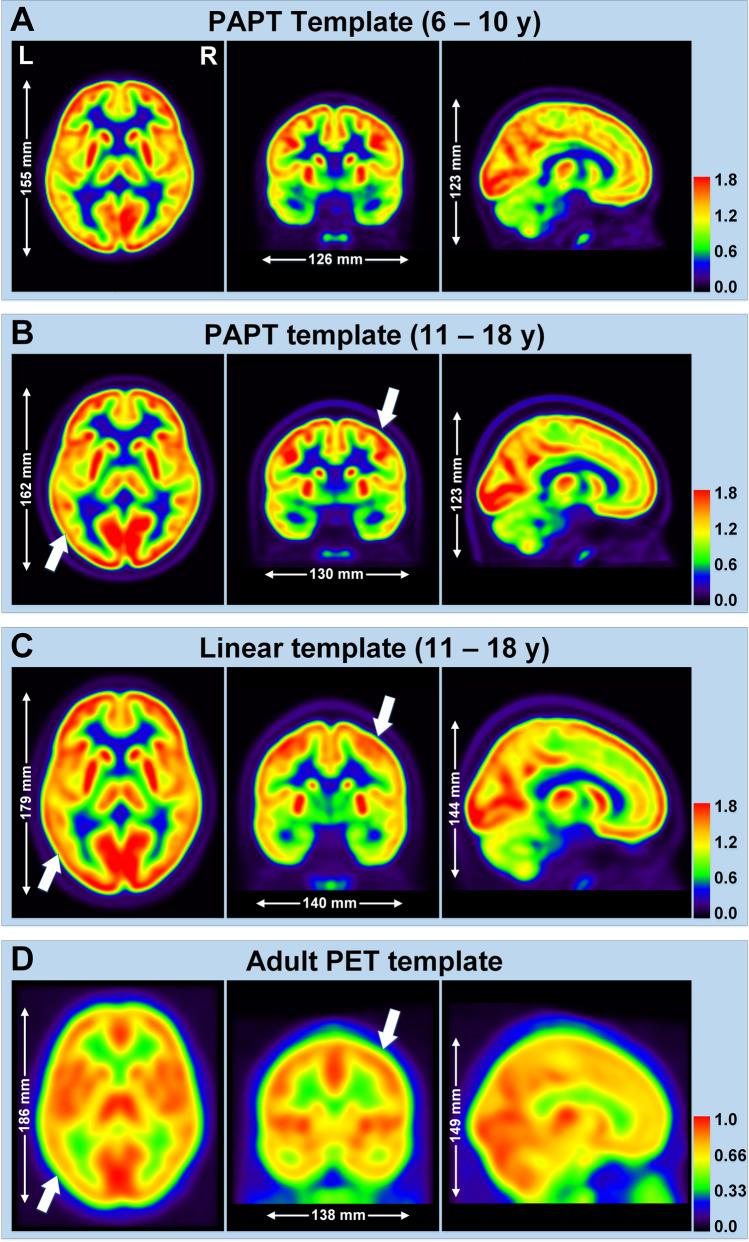

Fig. 2.

Comparison of PET templates. A 6–10 years PAPT; B 11–18 years PAPT; C pediatric linear template; D adult PET template. Arrows point blurred cortical structures in linear and adult templates

The 6–10-year PAPT was developed from 17 PET/CT controls (4 girls and 13 boys, mean age = 8.31 years) and the 11–18-year PAPT from 50 PET/CT controls (17 girls and 33 boys, mean age = 14.69 years) (Fig. 2A, B). Brain parcellation of PAPT is shown in Supplementary Fig. 1, and convergence process in Supplementary Fig. 2. The 6–10-year PAPT had smaller length (155 mm) and width (126 mm) than the 11–18-year PAPT (length = 162 mm, width = 130 mm) and both had the same height of 123 mm. Compared with PAPT, linear and adult templates had larger brain sizes and more blurred structural details (Fig. 2C, D).